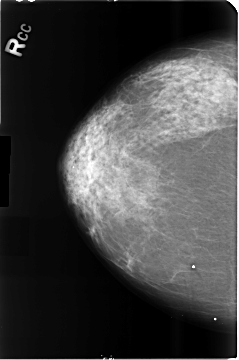

B_3514_1.RIGHT_CC

RIGHT_CC LINES 4680 PIXELS_PER_LINE 3104 BITS_PER_PIXEL 12 RESOLUTION 50 NON_OVERLAY